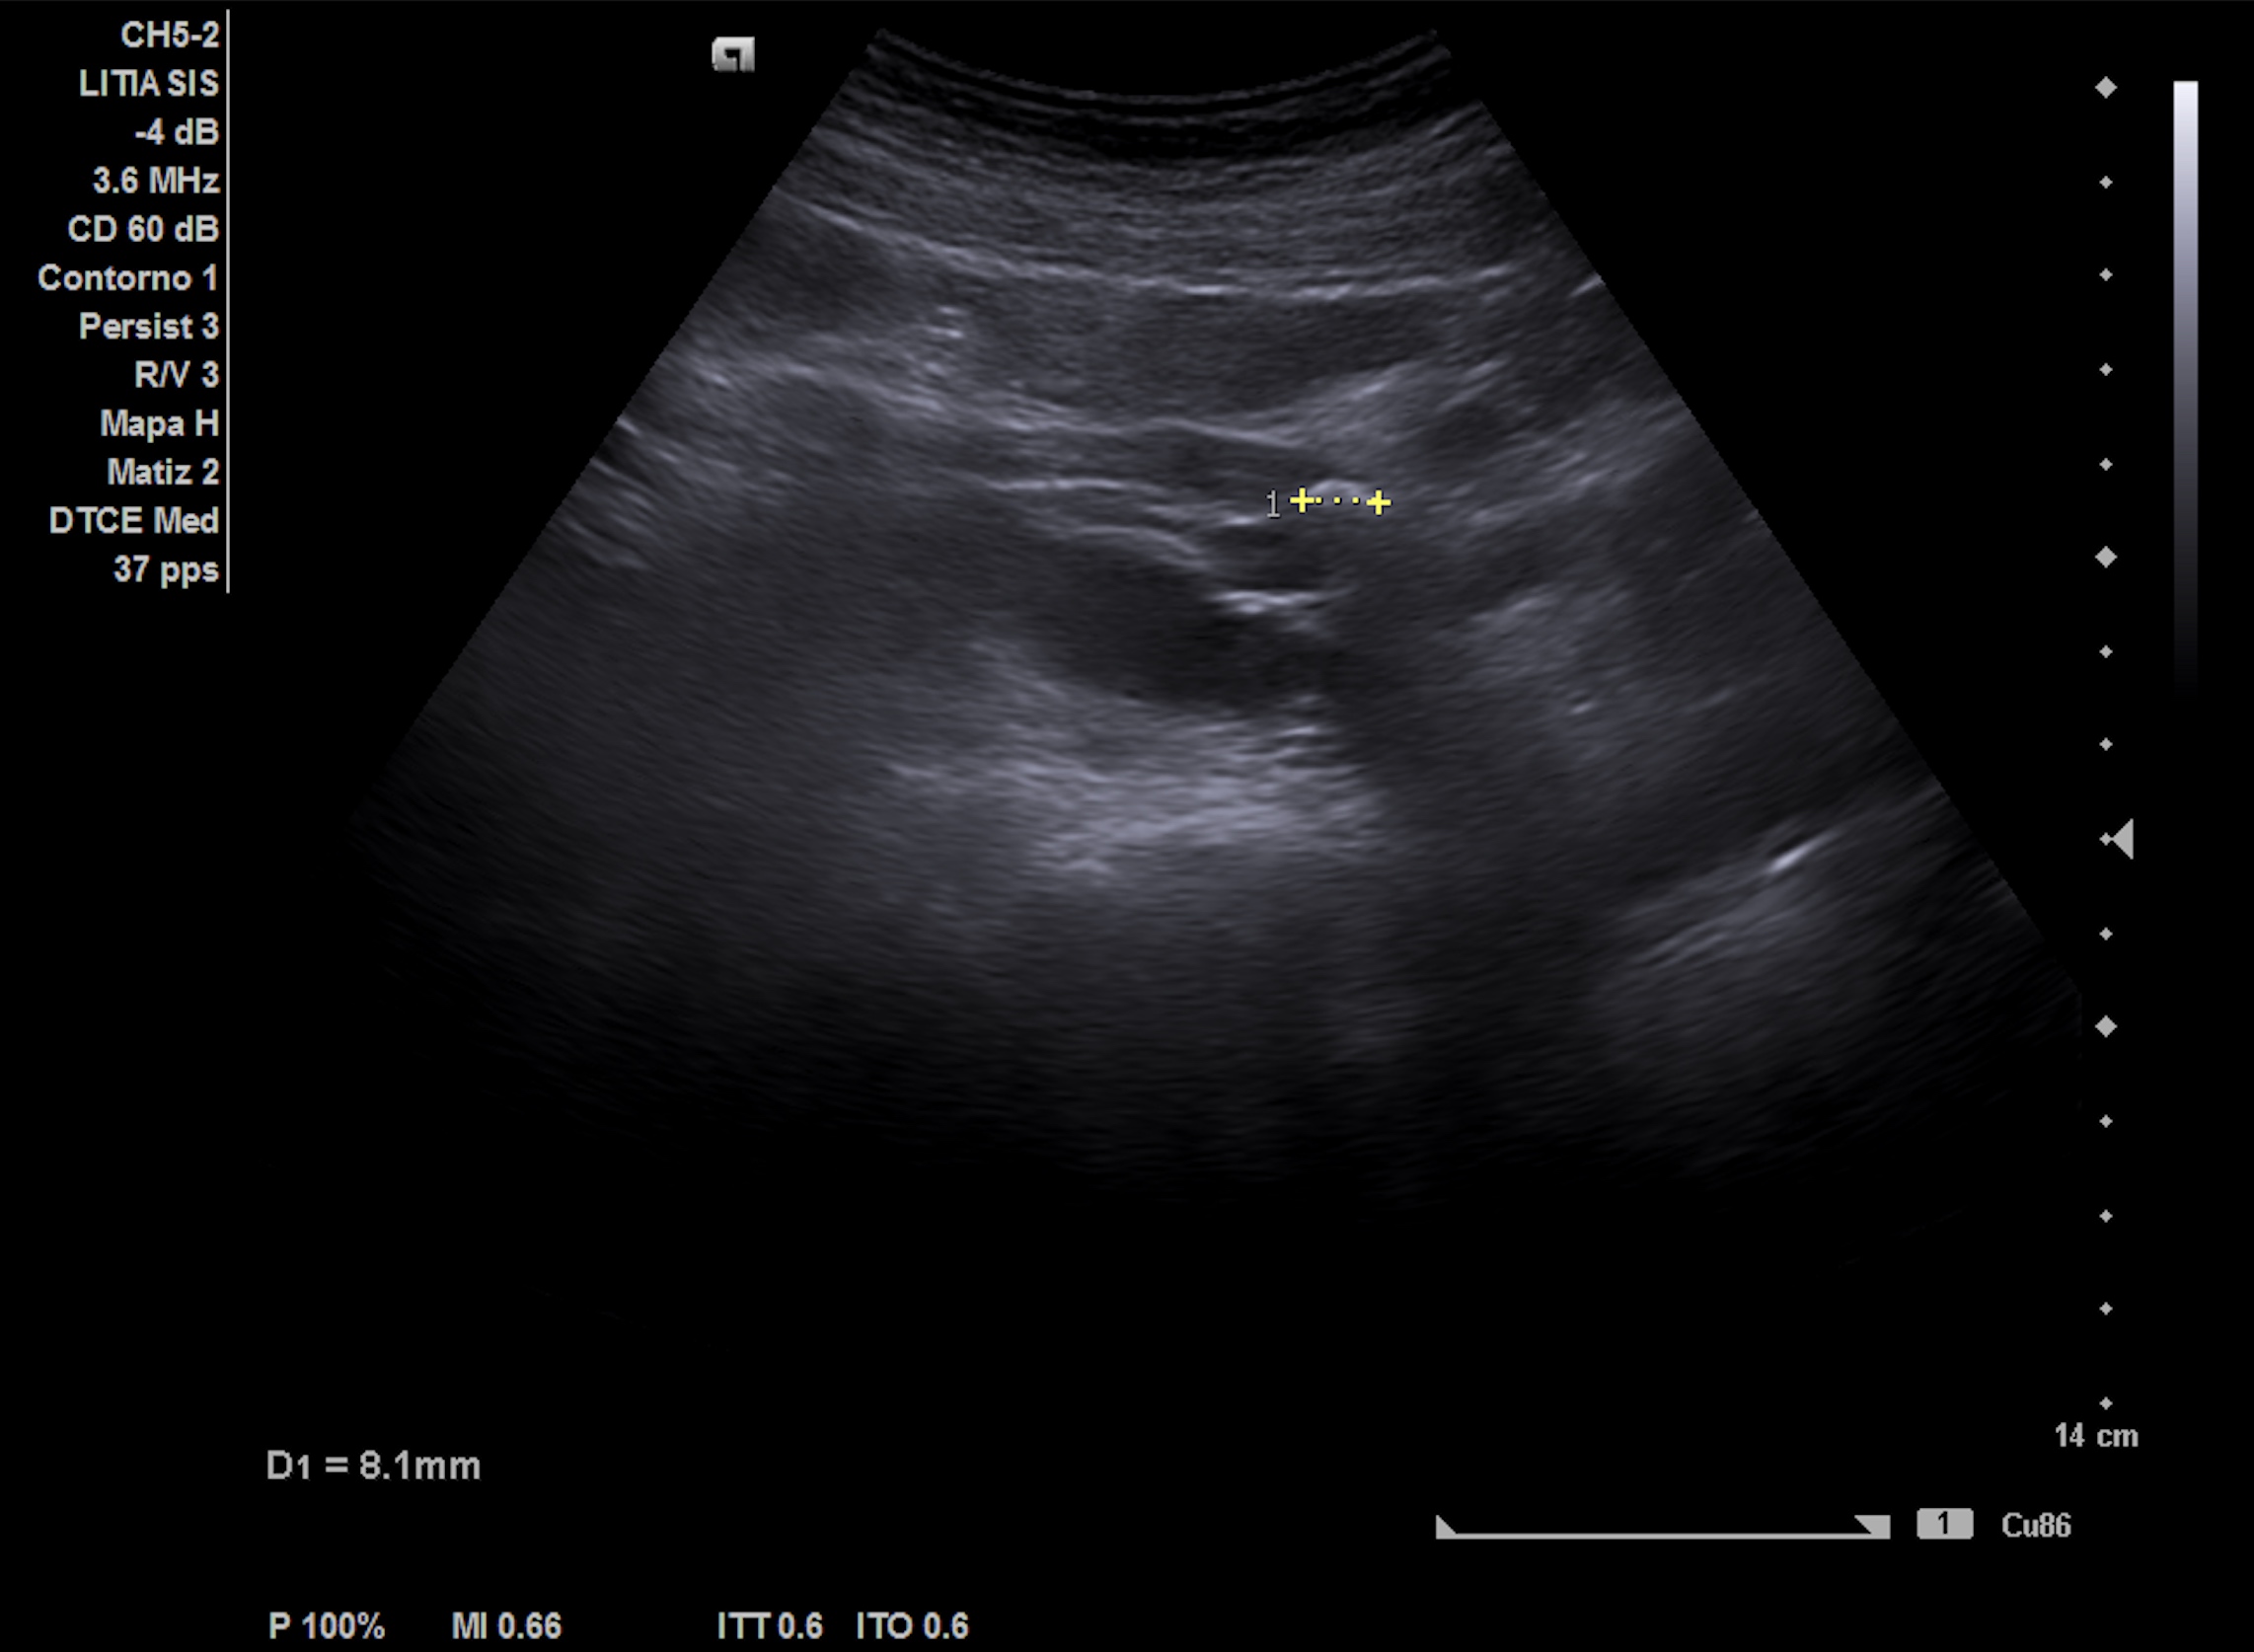

Nueva ecografía clínica renal, vías urinarias y vejiga (a la semana): hidronefrosis grado II que no presentaba hace 1 semana, no nefrolitiasis en cálices renales. Jet ureteral dcho permeable, en zona intermedia de uréter dcho presenta cálculo de 8 mm enclavado en el cruce de los vasos ilíacos con uréter.

Ecografía abdominopélvica urgencias hospital: Ureterohidronefrosis grado II derecha secundaria a litiasis de 7 mm en el uréter medio. Quiste cortical simple de 2.6 cm en el polo inferior.

Cólico renoureteral derecho por ureterolitiasis con hidronefrosis grado II con concordancia con el hospital.